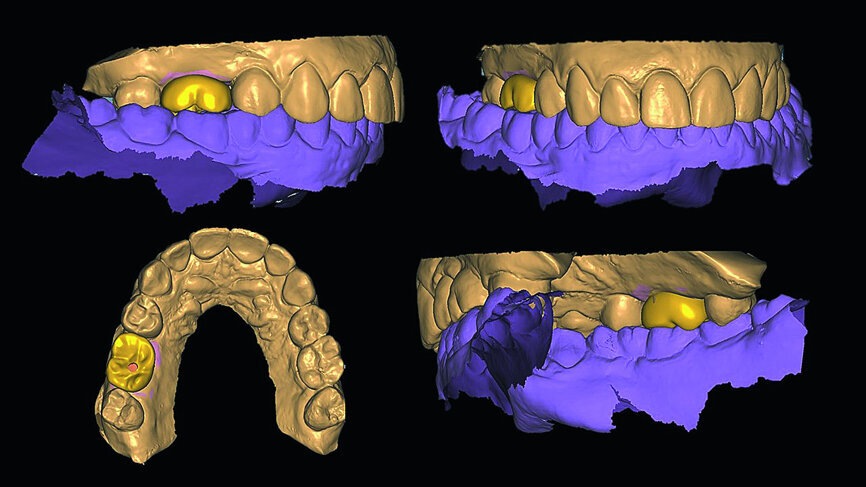

In March 2018, four months after the surgery, the prosthetic phase was started. An impression was taken with an intraoral scanner (CS 3600, Carestream Dental) using scan bodies for an impression at the implant head (MegaGen; Figs. 11a & b). The information was sent to the Anatomic Lab, where a crown was designed using a CAD programme. After the design of the crown had been finished, the information was sent to a milling machine (Amann Girrbach) and the crown was milled (Fig. 12). One week after the preparation, the definitive crown in monolithic zirconia was attached and the occlusion tested using T-Scan technology (Tekscan; Figs. 13a–c & 14).